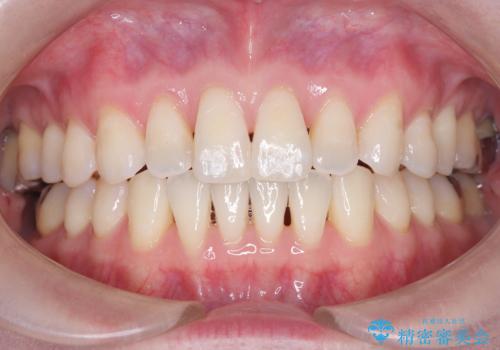

右下第二小臼歯の舌側転移の改善

- 患者様は、右下第二小臼歯が舌側に転移していることが主訴でした。診断の結果、抜歯を伴う矯正治療も検討しましたが、奥歯の遠心移動とIPR(インタープロキシマルリダクション)を行うことで、非抜歯で矯正を進めることが可能であると判断しました。治療計画では、審美ワイヤーを用いた2年間の治療で、歯列を整えつつ、臼歯関係や正中のバランスを維持しながら進めました。

非抜歯矯正では、歯の動きを慎重に調整することが求められます。本症例では、奥歯を遠心に移動させることで、舌側に転移した右下第二小臼歯の位置を改善しました。また、IPRを行うことで歯間スペースを確保し、無理なく歯列の調整を行いました。非抜歯での治療は、特に臼歯関係や正中を保ちながら治療できるというメリットがあり、最終的にはバランスの取れた歯並びを実現できました。審美ワイヤーを使用したことで、治療中も目立ちにくく、患者様の見た目にも配慮した治療を行いました。